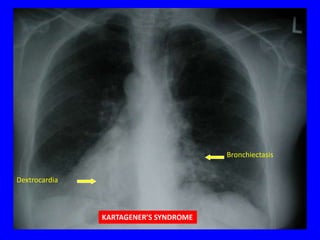

Bronchiectasis

Dextrocardia

KARTAGENER’S SYNDROME

Dilated

bronchus